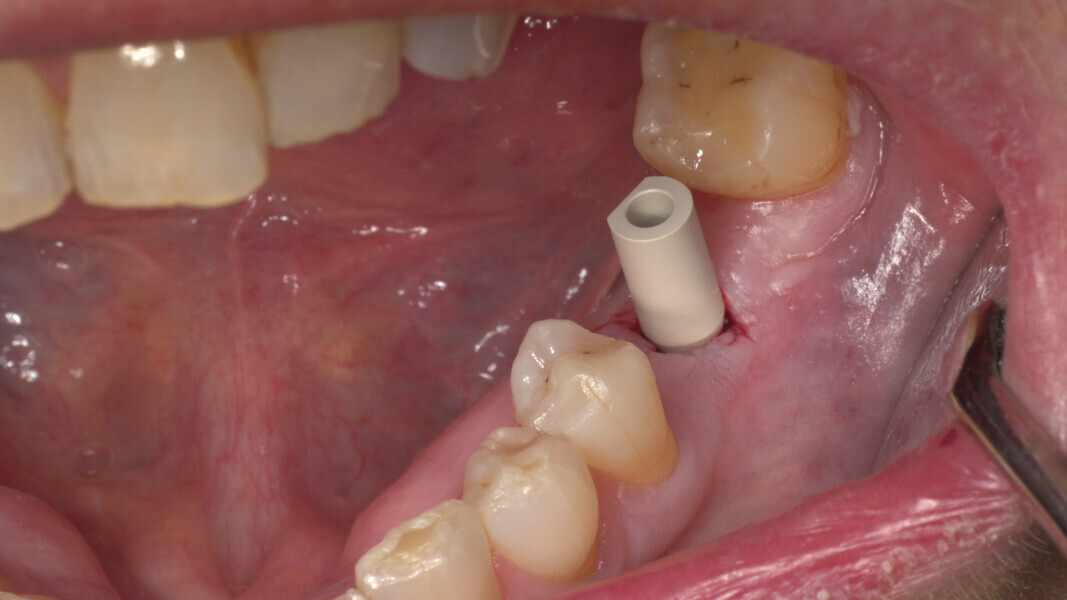

Conventional and immediate loading with final n!ce screw-retained crowns